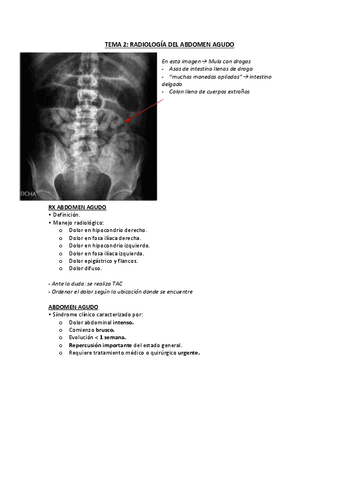

Apuntes - TEMA-2-RAYOS-ABDOMEN-AGUDO..pdf